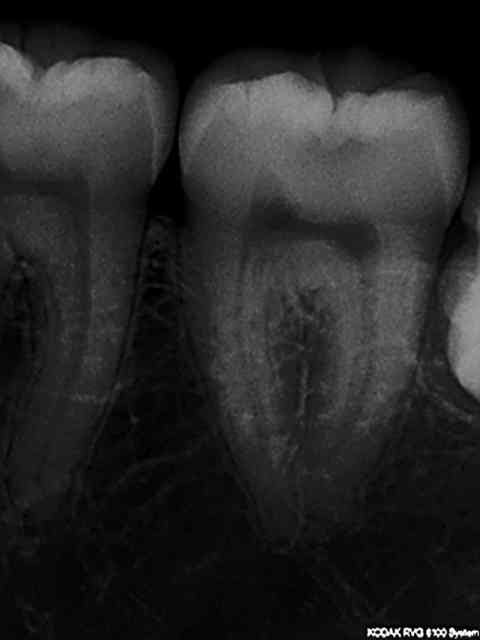

Radio initiale, cone en place , cone scellé, radio du bouchon apical réalisé au système b, puis radio finale après thermo-condensation. C'est obligatoire avec la nouvelle CCAM. Fini de jouer au dentiste le 1er juin.)))))))

Elles sont dans le désordre , remets les en ordre ( ca fait partie d'un qcm de formation continue) vu que le niveau de la formation initiale semble resté bloqué dans les années 80.